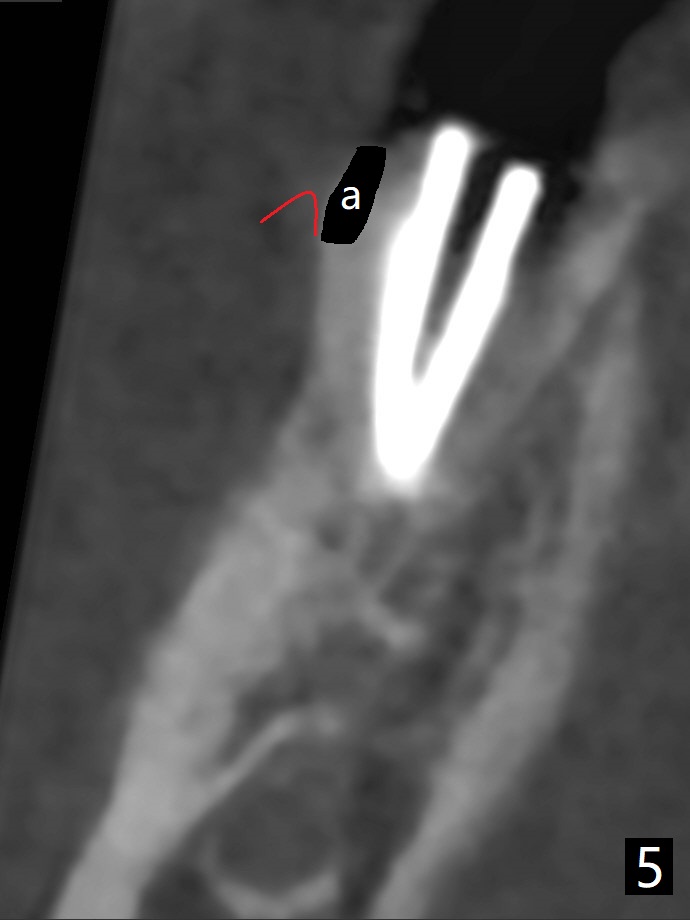

The tooth #30 of a 47-year-old woman has lower buccal crest (Fig.1-3 ^). To prevent post-extraction buccal plate collapse, closed socket shield (Fig.6,8-10 *) will be conducted in the mesial (Fig.1,4-6) and distal (Fig.2,7-10) roots. To decrease vibration, the buccal edge of the roots will be trimmed first (Fig.5,6 a) before root section (Fig.6 b).